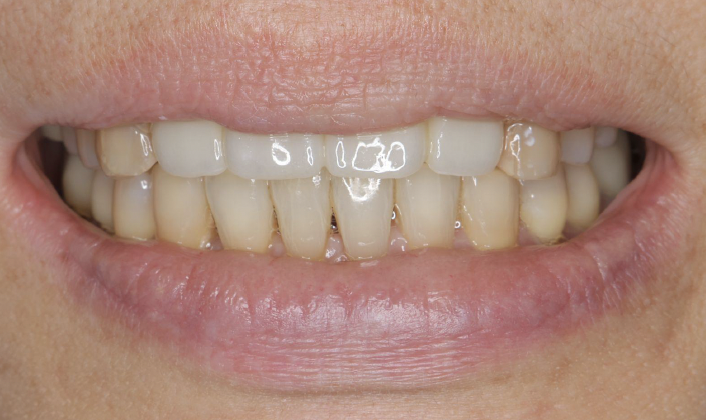

50代女性です。歯周病で歯の揺れが治まらず、前歯4本の抜歯となりました。

手術直後、1週間後の抜糸時、3か月後の写真です。